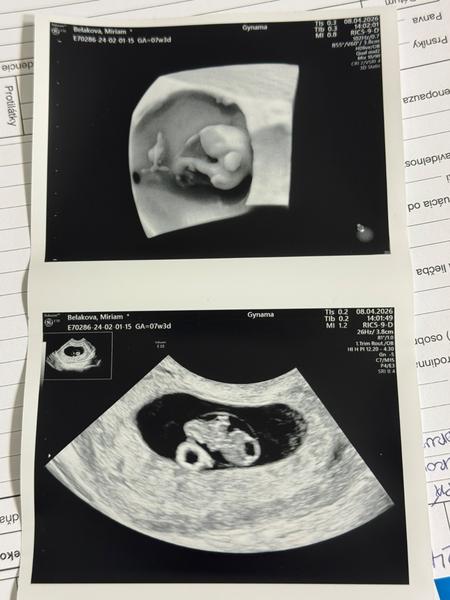

Prvý ultrazvuk: Možné určenie pohlavia dieťaťa?

Jedine z vesteckej gule 🙂 Ani v 16tt si lekari nie vzdy su isti a to ma babo okolo 9-10cm, a tvoje mimi ma zatial iba 1,5cm. Dolezite je zdravie, nie pohlavie